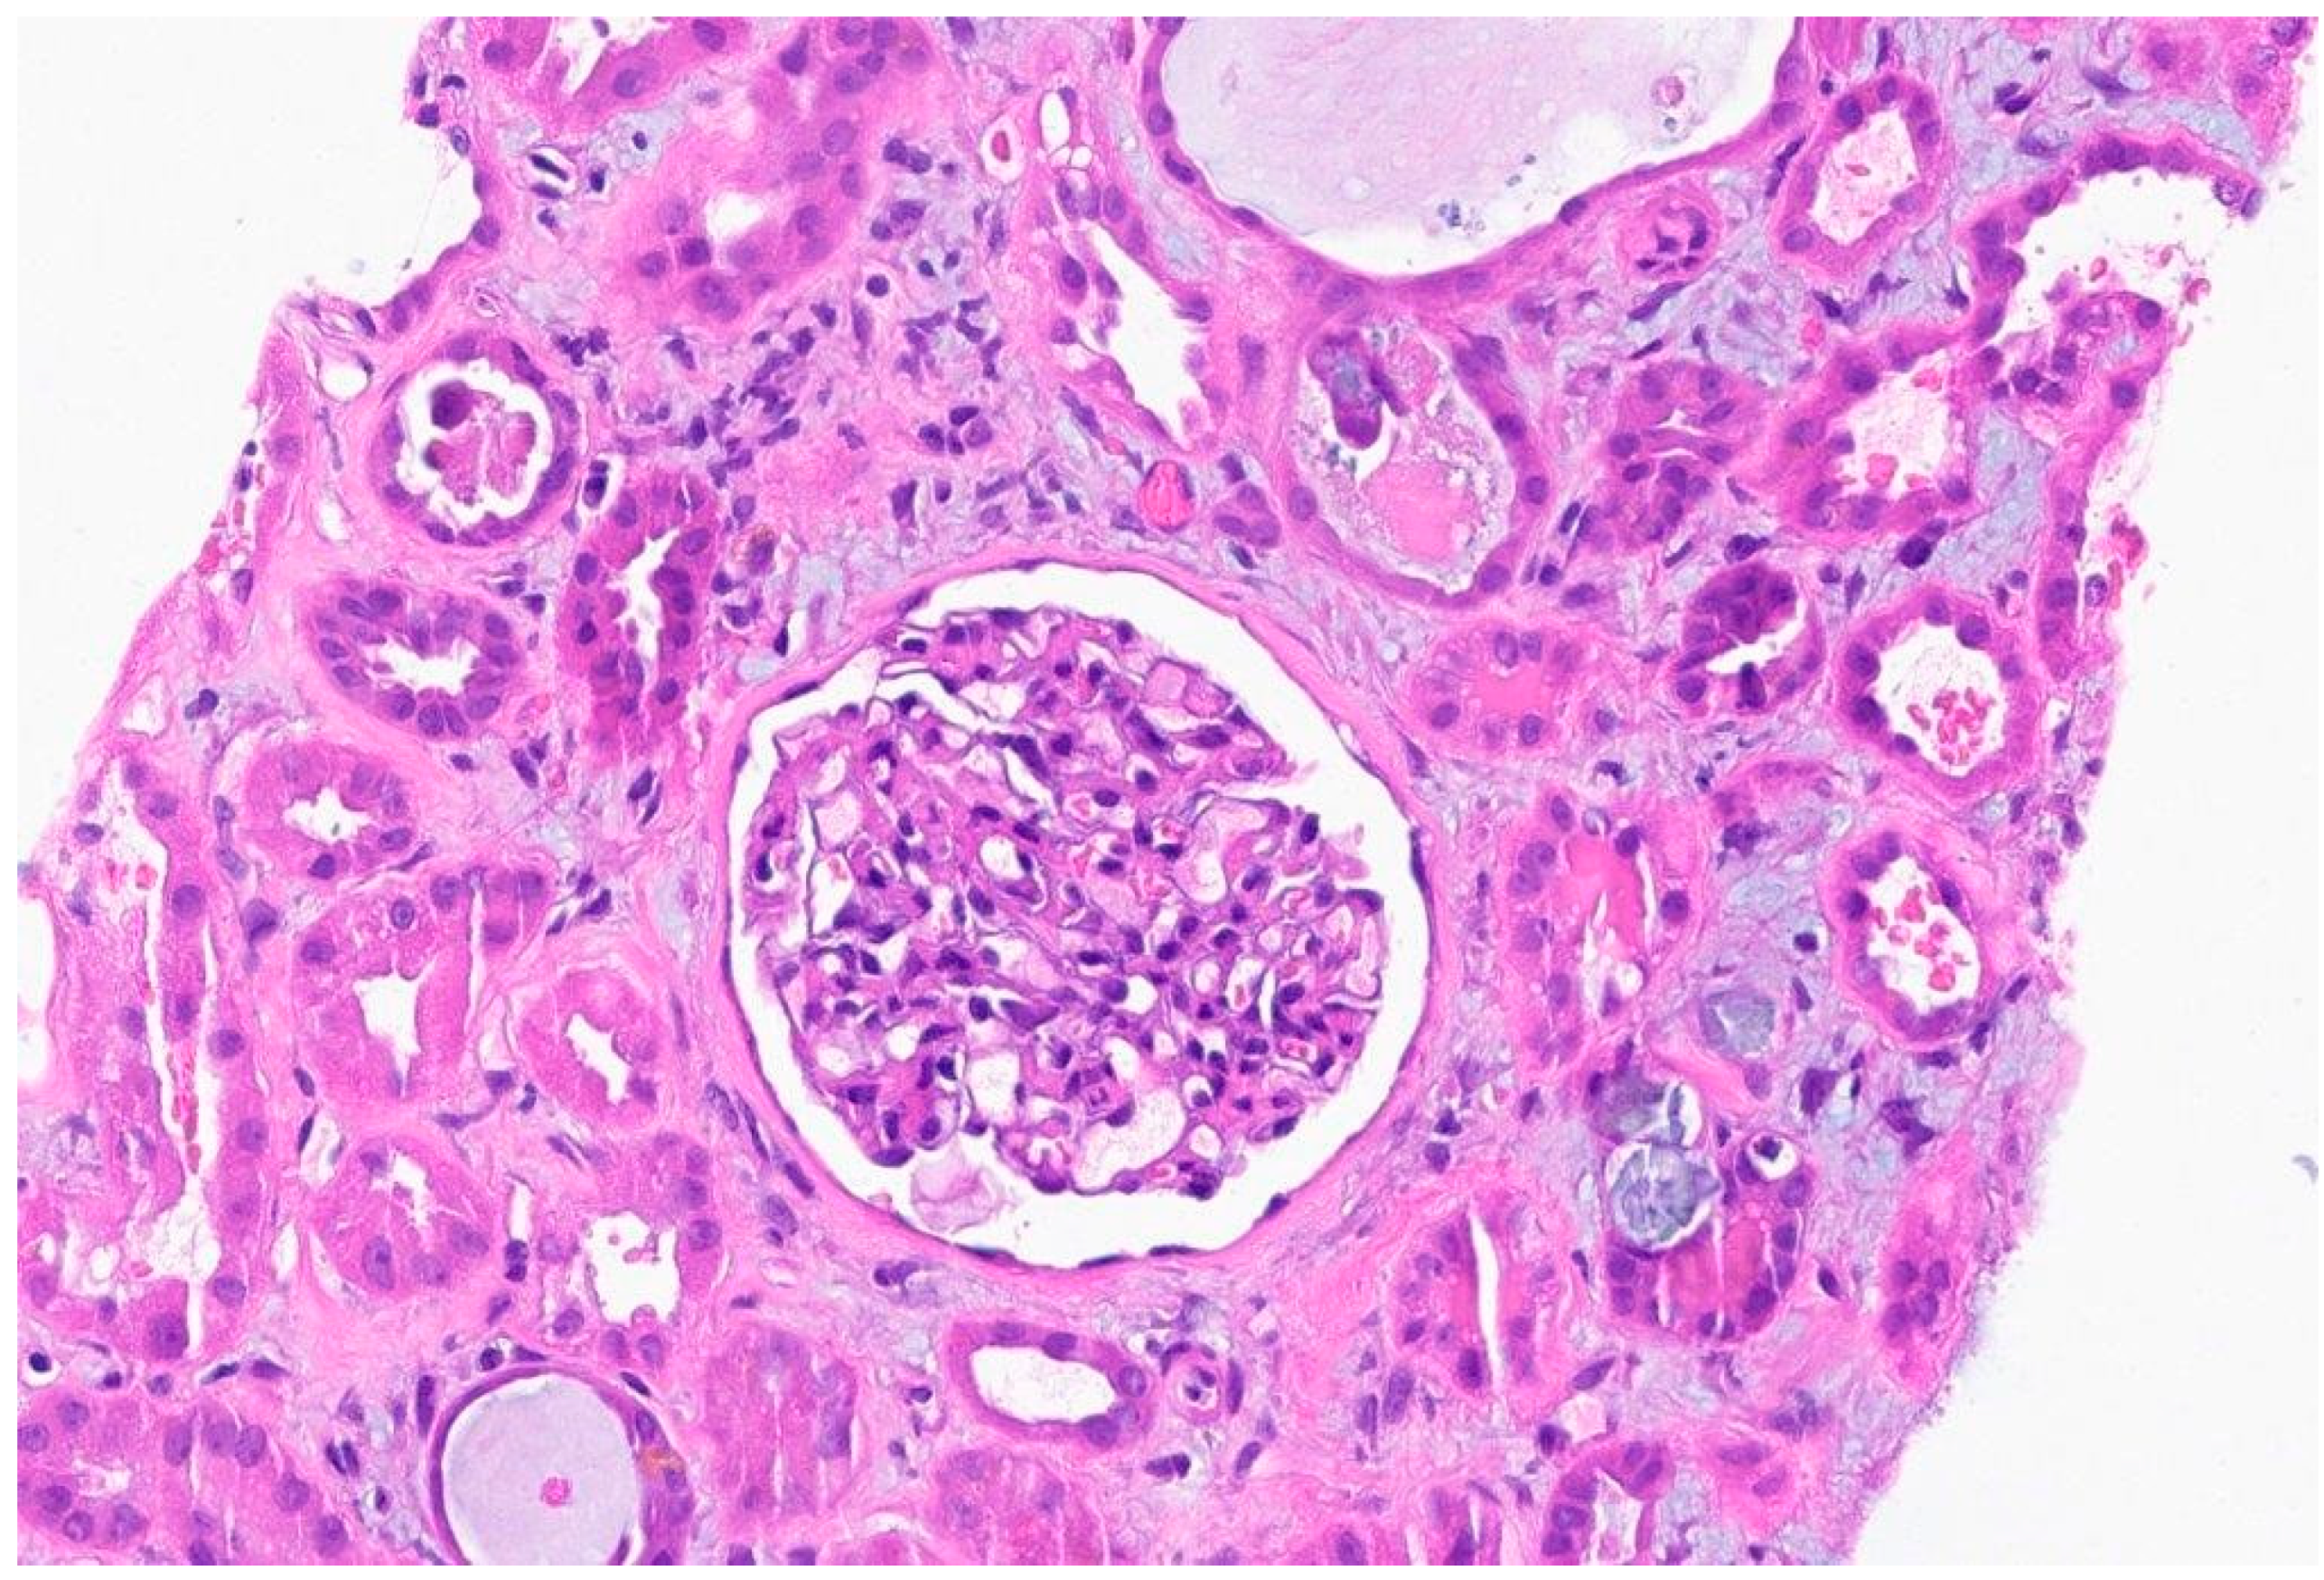

Figure 2. There is necrotic debris in two tubular lumens (lower left and upper right) and inspissated Tamm-Horsfall protein (center)on severe inflammatory background.

TUBULES AND INTERSTITIUM: There is severe diffuse interstitial edema involving cortex and medulla. There is severe tubular epithelial cell injury with luminal ectasia, fraying of the brush border, and simplification of the lining epithelium. Tubular lumina contain necrotic debris, and some lumina contain hyper eosinophilic ropy casts. The interstitium contains dense infiltrates of lymphocytes. Some areas contain aggregates of eosinophils. Mild tubulitis is seen. There are intratubular oxalate crystals (at least 3).

Electron Microscopy: Normal cellularity and mildly expanded mesangial regions are confirmed. No immune complex or paraprotein-related deposits are seen, and the glomerular basement membranes show wrinkling of several of the segments, but otherwise show no ultrastructural abnormalities. There is mild foot process effacement present. Examination of the tubulointerstitial compartment shows interstitial edema, severe interstitial inflammation, and multifocal tubulitis. No tubular basement membrane deposits are seen.